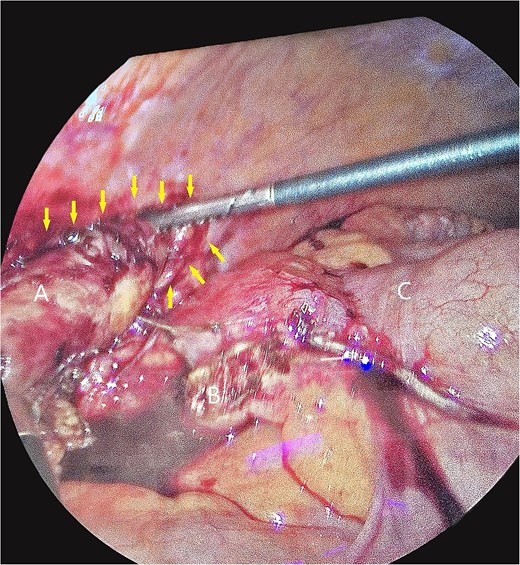

A 58-year-old female with a history of ovarian cancer, status post total abdominal hysterectomy, bilateral salpingo-oophorectomy, and omentectomy, presented with a 1-week history of right lower quadrant and right pelvic abdominal pain. Her labs were unremarkable. A CT scan of the abdomen and pelvis revealed a distended, fluid-filled appendix measuring 1.7 cm in diameter, with associated mesenteric infiltration and several small lymph nodes in the right lower quadrant, consistent with acute appendicitis (Fig. 1). The surgeon’s review of the scan was suspicious of retrocecal appendix (Fig. 2).

Axial images of CT scan with IV contrast showing appendix within retrocecal position in proximity within iliacus space. (A) Appendix; (B) iliacus muscle; (C) cecum.

Coronal image CT scan with IV contrast with arrows denoting appendix in proximity to iliacus space. (A) Appendix.